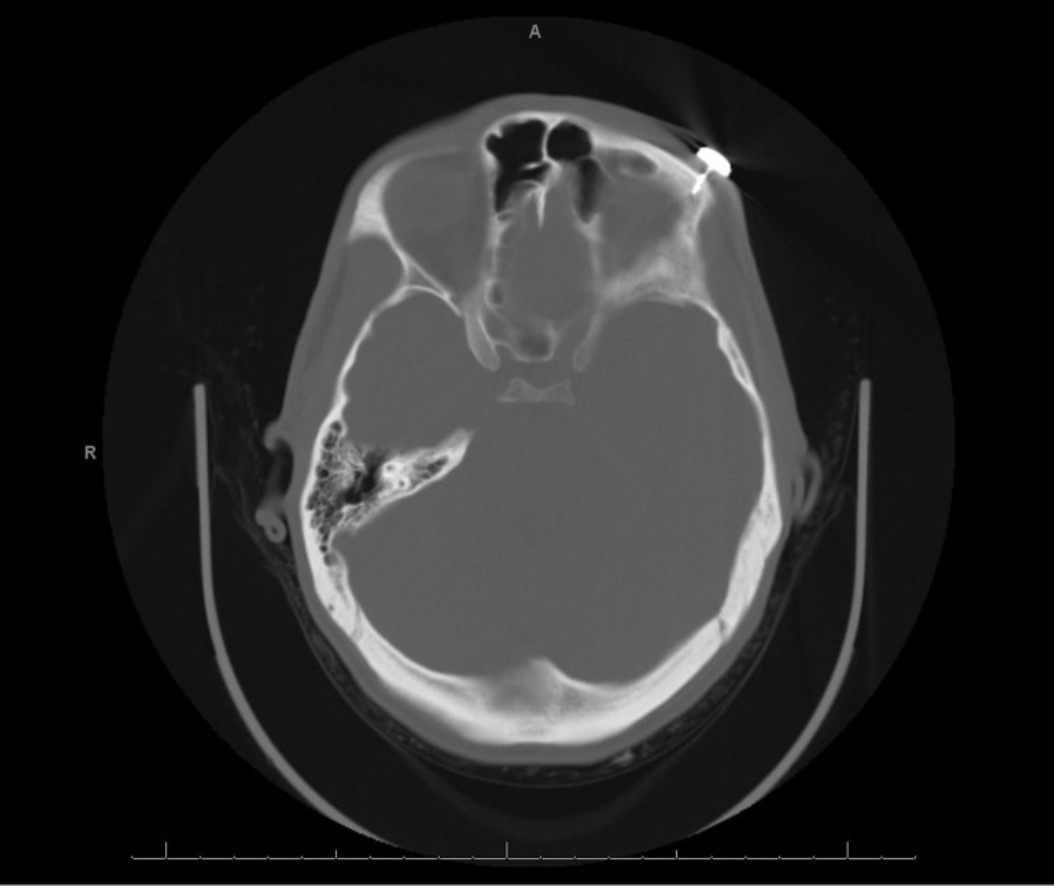

A 25-year-old man evaded apprehension by law enforcement, necessitating the user of a TASER 7. This resulted in 1 barb penetrating the left upper leg and another being embedded just above the left eyebrow in line with the lateral canthus (Figure 1). The patient was taken to a community hospital, where the barb from his left thigh was removed. However, upon attempted removal of the barb embedded above the brow, the cylindrical cartridge became detached and the barb remained embedded in his left forehead. Further attempts at extraction of the barb failed, prompting transfer to a tertiary hospital for facial trauma evaluation. Non-contrast head computed tomography (CT) imaging revealed a metallic object lodged in the left supraorbital soft tissues, with a 6-mm linear structure projecting into the supraorbital frontal bone. The scan also showed a small amount of adjacent subcutaneous gas, a left occipital scalp laceration, and no intracranial hemorrhage or ocular trauma (Figure 2).

Figure 2. Image of the axial computed tomography scan showing penetration of the supraorbital frontal bone.